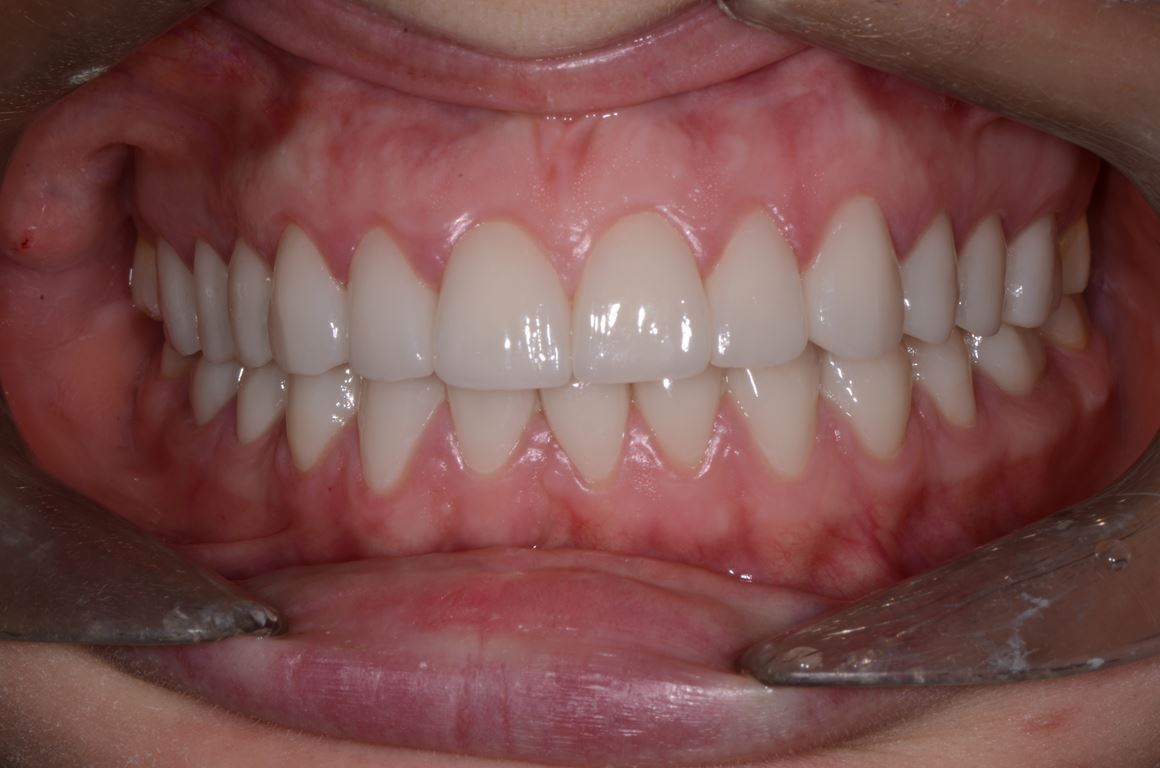

W pierwszym etapie diagnostycznym wykonano zdjęcia zewnątrz- i wewnątrzustne (ryc. 1-12).

Ryciny 39-50 przedstawiają stan po zakończeniu leczenia.